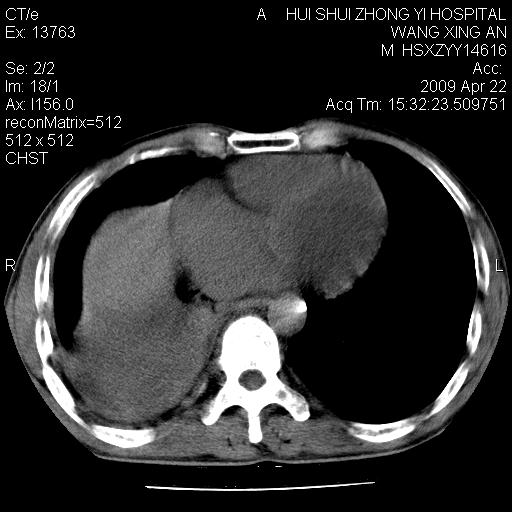

标题: CT19534:患者男、46岁咳嗽、胸痛半月。 [打印本页]

标题: CT19534:患者男、46岁咳嗽、胸痛半月。

中央型肺癌,右侧腹水

1、右下肺中央型肺癌并右肺转移,右肺下叶不张。(肿块围绕右肺下叶支气管生长,致管腔闭塞右肺下叶不张;右肺有结节影)。

2、右侧胸腔积液。